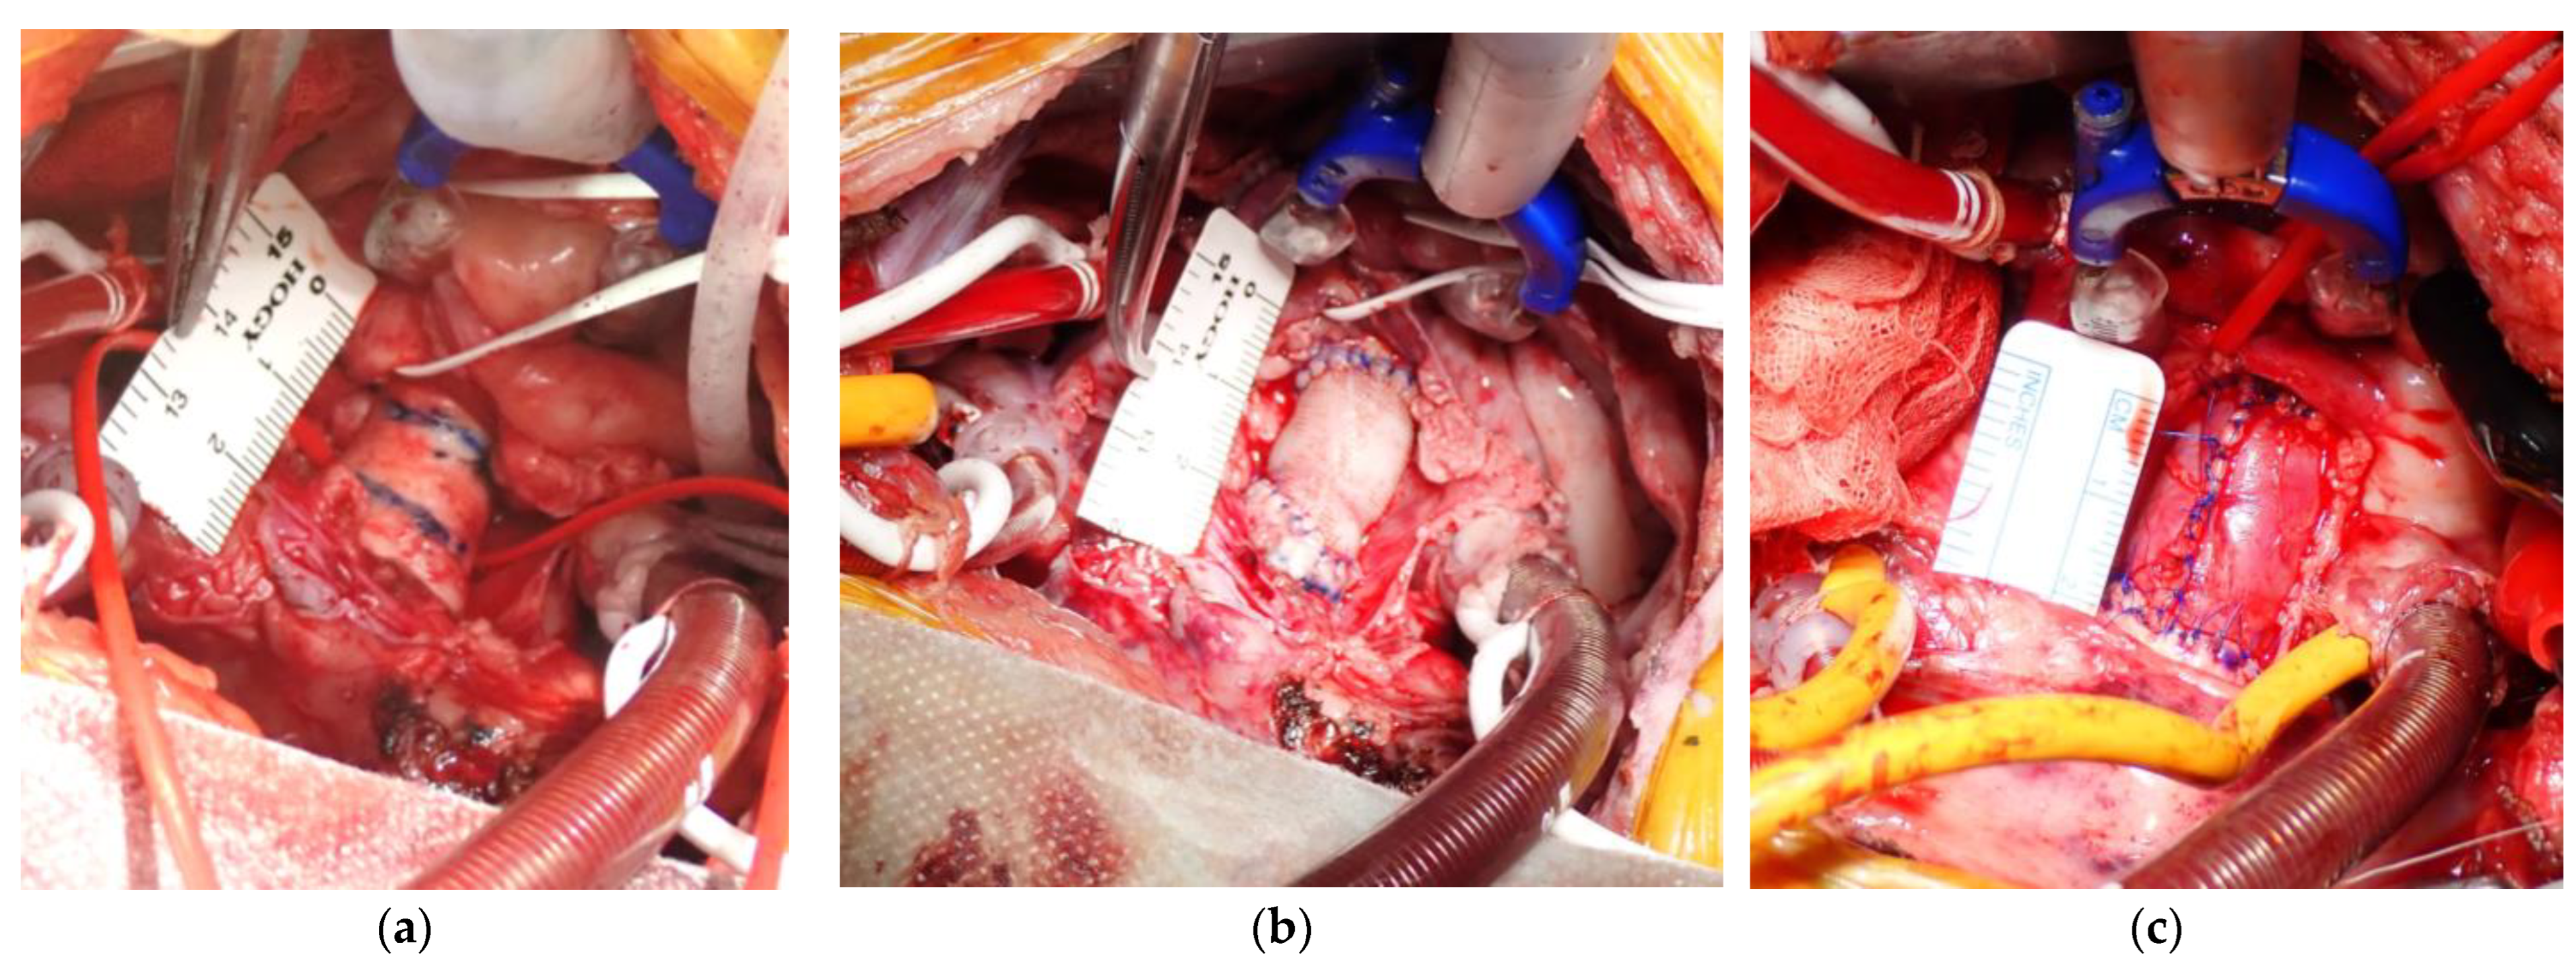

2.2. Aortic Replacement Procedure

3.1. Procedural Results